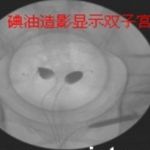

我是一个病情比较复杂的患者我的年龄也比较大,40多岁了,窦状卵泡直接几乎都没有了。我也有子宫腺肌症特别严重,肚子疼的就是死去活来的那种,做手术的时候整个子宫就跟烂苹果一样都被烂掉了,当时情况严重做了两次手术在北京安太医院。我还有甲状腺疾病,激素指标高的高低的低,都特别严重。我的免疫也有问题。这些问题都是在我们大西北没有查出来,也没有办法治疗,耽误了我十多年。

后来我在北京安太医院做了两次腺肌症手术后我就怀孕了,怀孕了之后到七八个月的时候,我又发现有流产的征兆,当时疫情我在老家,这几年看病也把钱花完了,本来打算去北京的结果也没有去成。后来我就赌了一把,当时我也肚子比较大,七八个月了,我在当地医院住了几天就出院了,回家就就用了陈凤林院长的那个倒立技术。我每天就躺在沙发上把腿都翘起来做倒立,一直坚持到了足月,38周加5生了这个宝宝。